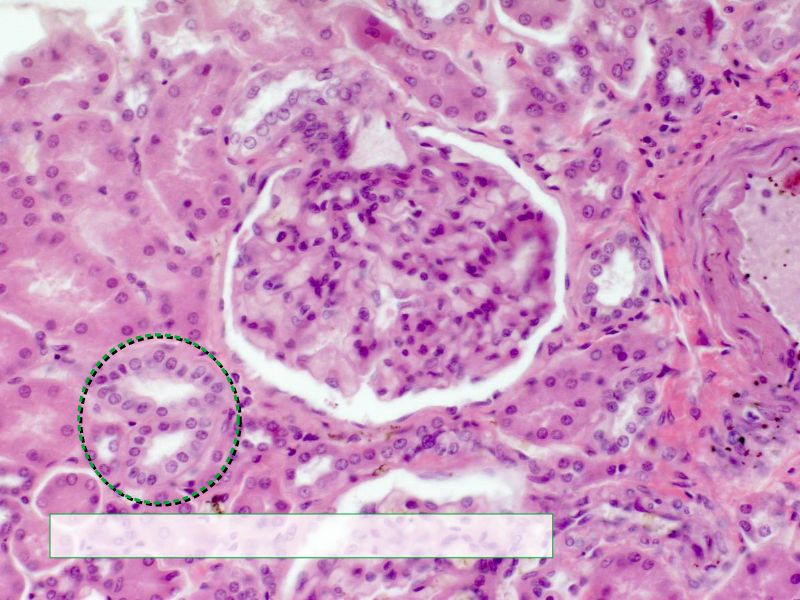

Podocytes

• Visceral layer of epithelium

• Protrude into capsular space

• Attached to basement membrane

• Long cytoplasmic extensions

• Primary processes

• Secondary processes

• Podocyte feet

• Tightly spaced

• Filtration slits 20 - 30 nm wide